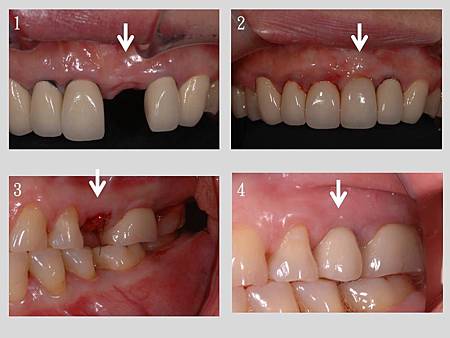

1.檢視牙套的內層, 使用含黃金成分的內冠

2.將精密研磨過的牙套與支台接著在一起(此時不需黏膠)

3.白線為骨頭高度, 沒有髒汙的殘膠刺激, 骨頭的高度就比較不會因為細菌的關係而流失

4.因為支台與牙套的接著點非常的深入牙齦下, 所以牙齒可以做比較自然的萌發外型, 這種植牙的牙套甚至美觀度會勝過自然牙的牙套, 可以在下面的Case看到驗證

1.支台鎖入已在病人口內骨整合之植體

2.將牙套固定於支台上, 可以觀察牙齦的顏色很自然

3.支台鎖入已在病人口內骨整合之植體

4.將牙套固定於支台上, 可以觀察牙齦的顏色很自然(前方為自然牙金屬瓷牙露出黑邊)

1.治療前

2.將牙套固定於支台上, 可以觀察牙齦的顏色很自然, 其他牙齒為自然牙的牙套(牙齦處內層的暗黑透出而不美觀)

3.治療前

4.治療後